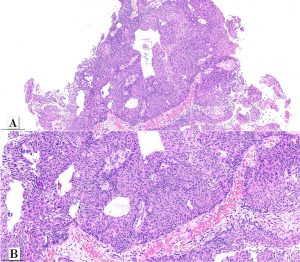

A male patient in his early 70s underwent surgical removal a single pedunculated 3 cm polypoid tumor in the bladder mucosa at the left lateral wall.

Papillary urothelial carcinoma, noninvasive, whorled subtype

One rare morphologic subtype of in noninvasive papillary urothelial carcinoma has been described as a whorled pattern. Patriarca et al. 2014 described a series of 12 patients: all noninvasive and most of them 11/12 classified as low-grade. One patient had a tumor with mixed grade (5% of the tumor at other areas. Whorled pattern shows concentrically organized cell structures, without morphological evidence of keratinization, similar to the whorling structures of transitional meningioma.

In that series, none of the cases experienced T1 stage progression and two recurrences occurred. One of the recurrent tumors was the one harboring small focus of high-grade tumor inside the primary lesion. Interestingly, the recurrent cases maintained the same whorling pattern in the second transurethral resection specimens. Therefore, although limited data on follow up is available, clinical behavior seems to be similar to low-grade noninvasive papillary urothelial carcinoma (Patriarca et al. 2014). Awareness of this morphologic subtype is important to avoid misclassification of other epithelial lesions which may show squamous or squamoid morphology.